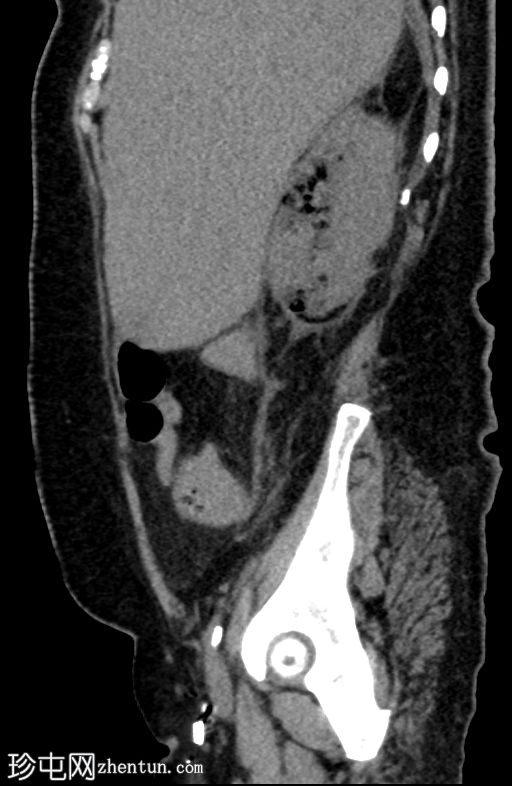

轴位

平扫

肾实质内可见多个气体囊,主要累及右肾中部和下极。

肾周脂肪组织中度炎症性改变,并可见条索状肾周积液。

气体未延伸至肾盂或输尿管。

无肾积水。

少量微小的非梗阻性肾结石(砂砾)。